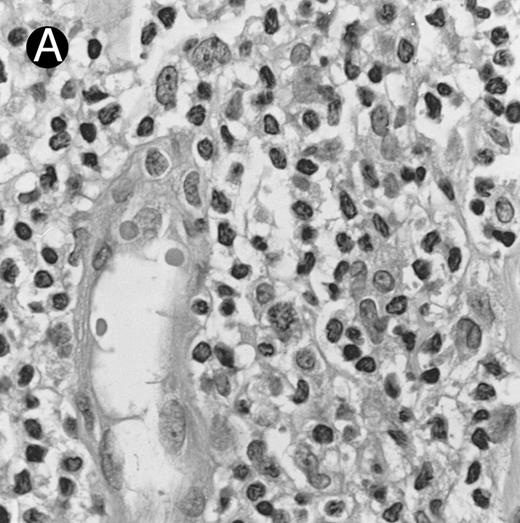

Lymph node biopsy of aggressive NK cell leukemia/lymphoma (case no. 37). There is a fairly monotonous, diffuse infiltrate of medium-sized cells with round nuclei. The neoplastic cells in this case resemble plasmacytoid monocytes.

There were very few to numerous granular lymphocytes in the peripheral blood. Some of the granular lymphocytes were indistinguishable from normal large granular lymphocytes, with round nuclei, dense chromatin, and pale cytoplasm with fine azurophilic granules (Fig 5A). Some granular lymphocytes had larger nuclei with more open chromatin and distinct nucleoli (Fig 5B); occasional nuclei could show indentations. The azurophilic granules were sometimes large and coarse. There were also circulating normoblasts and immature myeloid cells. Marrow involvement ranged from subtle to extensive. In histologic sections, irrespective of site, there was a monotonous infiltrate of medium-sized cells with round nuclei and fairly condensed chromatin (Fig 6). Karyorrhexis was prominent. The infiltrate was diffuse, interstitial, or angiocentric.